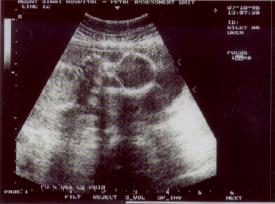

Diana, the nurse, said she would do a quick ultrasound to show us

all was okay. Now I had asked for an image the last 2 visits, but something

came up each time, and the nurse ended up having more important things

to do. But this time, with things a little more relaxed, she was able to

"click" off the below pictures:

Abigail

&

Boris

What you are seeing, is the head of each of the babies. With Abigail,

it is easier to see her body extending off to the left! But in both cases,

it looks like they are wearing Halloween masks!